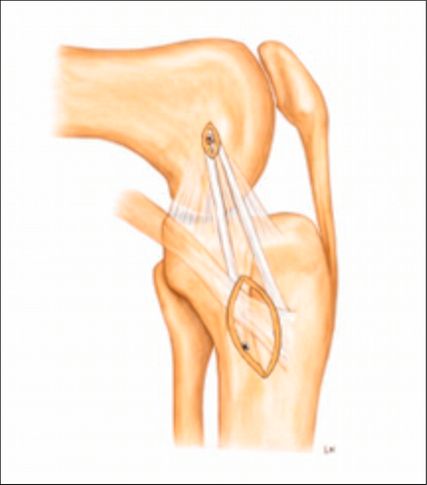

Anteromediale Tenodese

Die anteromediale Tenodese unter Verwendung der gestielten Gracilis- oder Semitendinosus-Sehne dient der Augmentation bzw. Rekonstruktion sowohl des tiefen als auch des oberflächlichen medialen Kollateralbandes (d/sMCL) über zwei funktionelle Bündel. Abhängig vom zugrunde liegenden Verletzungsmuster kann der Eingriff über einen minimalinvasiven oder einen offenen Zugang durchgeführt werden. Die Technik eignet sich bei akuten Eingriffen in Kombination mit einer MCL-Naht bzw. Refixation im Sinne eines „Bio-Brace“. Darüber hinaus kann sie bei chronischen Fällen mit leichter bis moderater anteromedialer Instabilität mit oder ohne VKB-Rekonstruktion durchgeführt werden. Der Ablauf eines solchen Eingriffes ist wie folgt: Die Sehne wird proximal mittels offenen Sehnenstrippers entnommen, während die tibiale Insertion erhalten bleibt. Die femorale Fixation der gedoppelten Sehne erfolgt im hinteren Anteil des nativen Ansatzes des oberflächlichen Längsbandes, während das freie Sehnenende im Zentrum der distalen tibialen Insertionsstelle des oberflächlichen medialen Kollateralbandes fixiert wird. Eine detaillierte Beschreibung der Operationstechnik ist über den QR-Code (Abb. 2,3) als Videoanleitung abrufbar.1